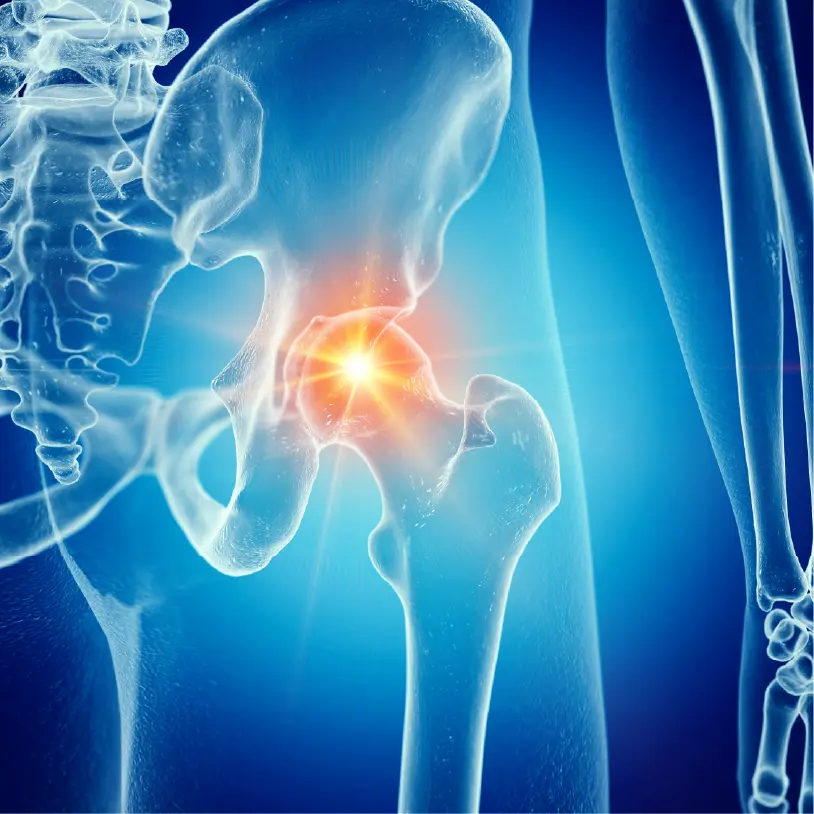

大腿骨骨折治療センター設立の原点は、私の祖母の骨折でした。

神奈川に住む90歳近い祖母が転倒し、大腿骨頚部骨折と診断されました。

その一心で、東京初となる大腿骨骨折に特化した“大腿骨骨折治療センター”を設立しました。